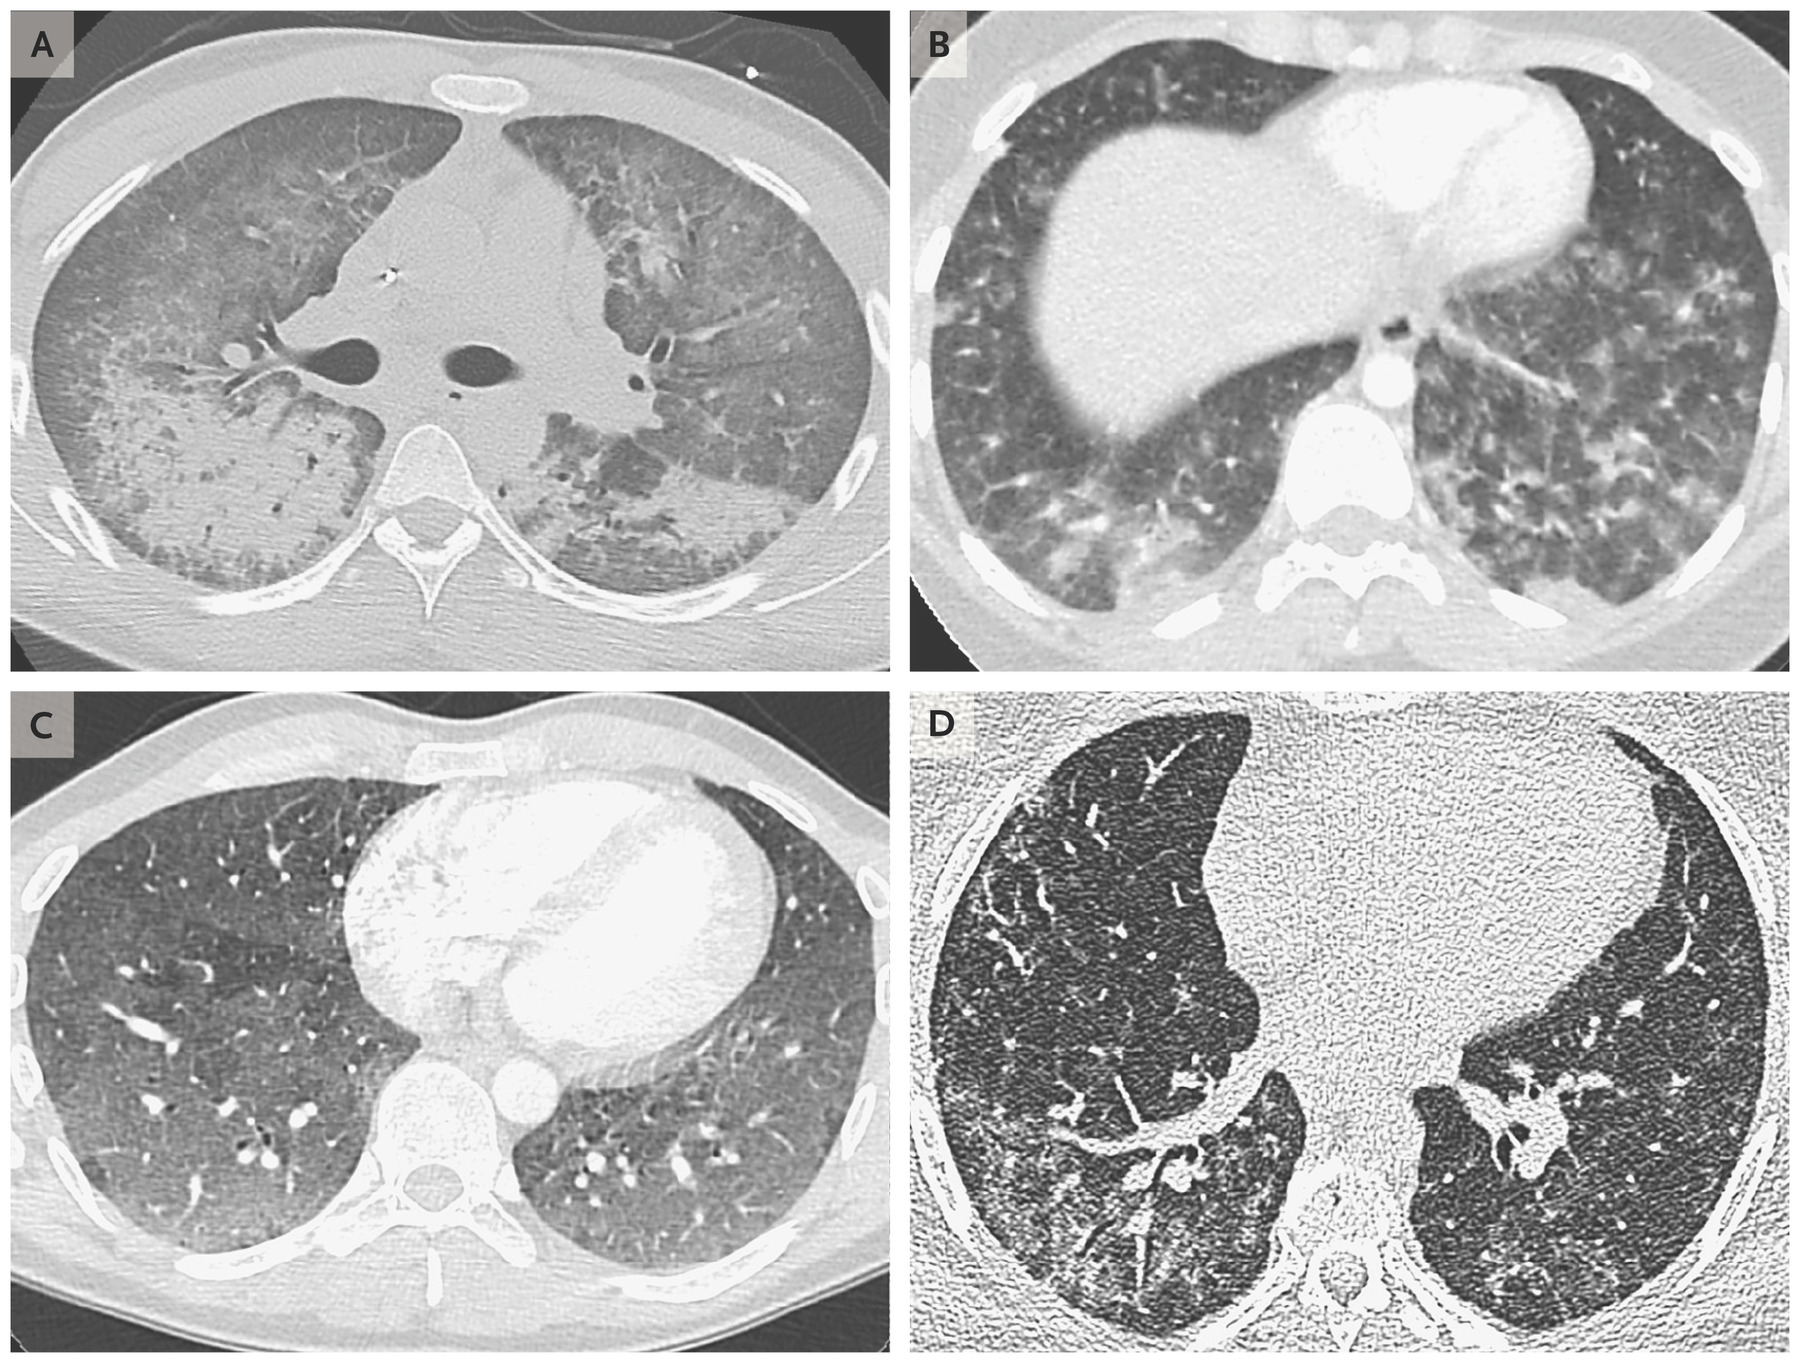

The New England Journal of Medicine reported scans of damaged patients lungs that is now known as Vaping-Induced Lung Injury. What seemed to be waves of the rumor is confirmed by hard evidence that there is damage caused by vaping.

Scans of the lungs of 4 patients, aged 19 to 49, showing damage to the lungs from vaping devices. (New England Journal of Medicine)